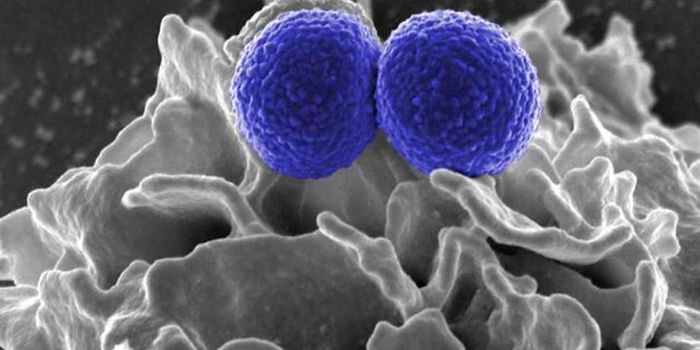

JUN 08, 2018MicrobiologyThe S. aureus pathogen doesn't only invade bone, it uses it as a snack.